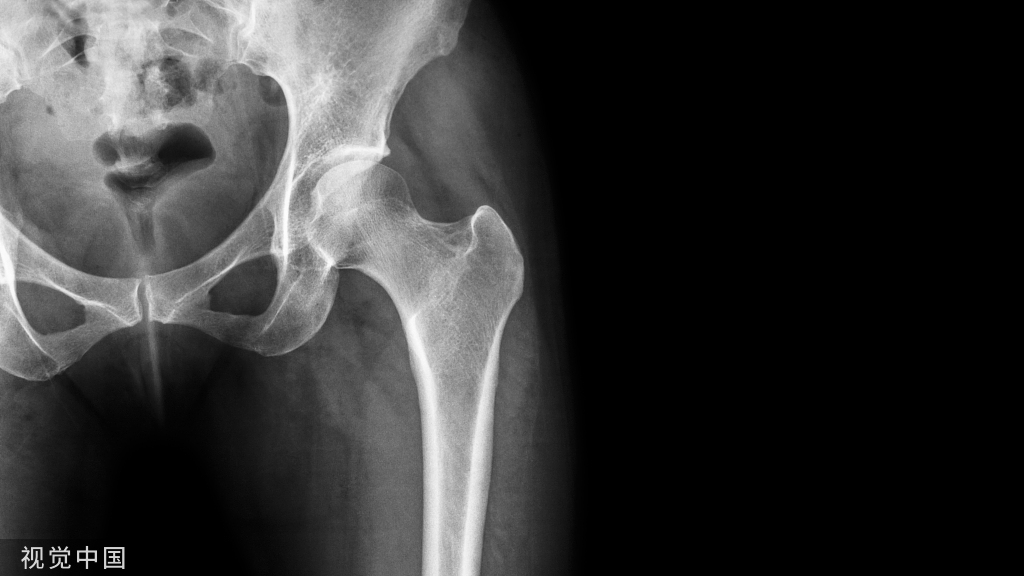

下肢牵引术

下肢牵引术应用比较广泛,从股骨颈骨折,转子间骨折,股骨骨折,到胫腓骨骨折等,都需要用到牵引。对于下肢骨折,两种牵引方法均可应用:皮牵引用于临时固定或术前稳定;而骨牵引多用于手术禁忌患者的治疗性措施。

Buck's(图 7)或 Russell's(图 8)皮肤牵引:在股骨骨折,转子间骨折或髋部骨折中应用广泛,下肢骨折使用皮牵引一般不能达到复位效果,但是可以在一定程度上减轻疼痛和保持局部肢体长度。